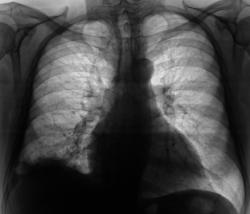

Пациент был направлен в рентгеновский кабинет терапевтом с диагнозом "Правостороняя пневмония". Было произведено стандартное исследование.

Было назначено противовоспалительное лечение. Через 1 неделю проведен "рентген-контроль".

Согласен с коллегой, но по-моему, кроме это выпот есть и заднем синусе. Картина в серия снимков №7-9, с небольшой положительной динамикой в сравнении данными в серии №4-6.

Кажущееся затемнение в области средней доли симулирует суперпозиция приподнятого правого купола диафрагмы и тени сердца. В заднем синусе справа - небольшой выпот, а со стороны диафрагмы, кроме элевации и выпрямления, присутствует картина диафрагматита в задних отделах. Вероятно необходимо ультразвуковое исследование органов брюшной полости и забрюшинного пространства для поиска первопричины данного состояния там. Динамика процесса за время наблюдения - явно положительная.